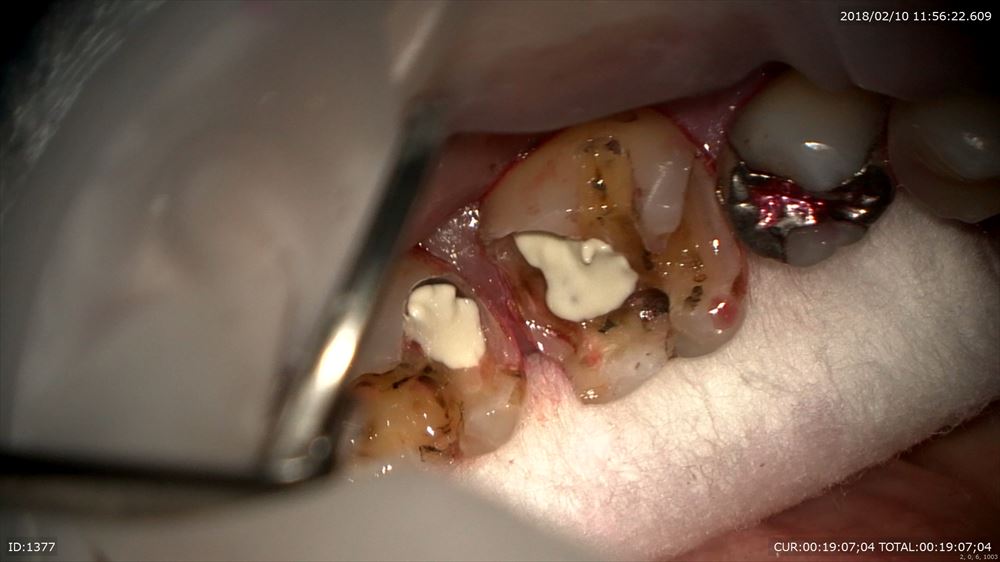

銀歯虫歯の方。

銀歯の中は

こうなっています。

これもマイクロスコープを使用し無痛で感染除去 MTAで

これで型とり。大丈夫!!